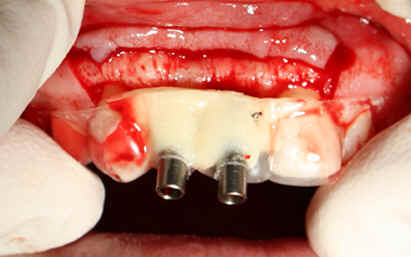

The adjusted stent fits well after raising the flap (Fig.14). Initial osteotomy is made using the stent. The osteotomy for #8 is located in the middle of the ridge labiolingually, whereas that for #7 is too lingual. Adjustment is made freehand. The final osteotomy is shown in Fig.15: 4.0 mm in diameter for #7 and 4.5 mm for #8. With direct vision (large exposure) and digital palpation, there is no perforation (not shown). There is concavity in the labial plate (arrowheads in Fig.15), which is corrected by connective tissue graft. The arrowhead in Fig.16 points to the suture that stabilizes the graft against the labial mucoperiosteal flap.